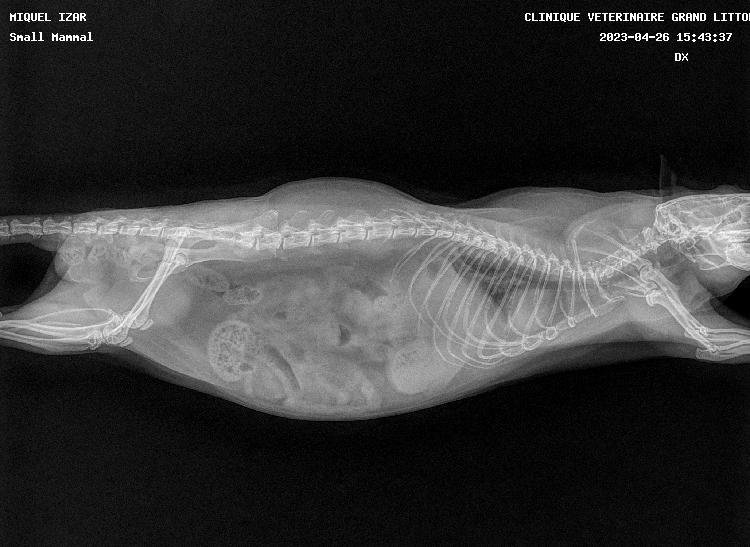

pas de super bonnes nouvelles car les deux miss ont les poumons atteints, si je m'en doutais un peu pour Izar qui ronflait depuis mars (c'est vite parti avec le collyre dans le nez) et respirait une peu trop vite, je suis tombée des nues pour Thari, qui me fait un coup à la Seren : zéro symptôme mais poumons pourris (si seulement elle pouvait avoir la même longévité :siffle:). Les deux pupuces sont donc sous deux antibiotiques (un par injection et un par voie orale) et Izar à en plus un AINS. Contrôle radio prévu dans quelques semaines.

Petites photos des belles et radios en spoil

Izar

Izarprofildroitavril2023.jpg.31a414688eda128425e73b46a0b65f38.jpg

Izarprofilgaucheavril2023.jpg.0eec5561fec0efb202ff549e6a77de8f.jpg

Thari

Thariprofildroitavril2023.jpg.5c18040e016999d23a3866f24f5c81e8.jpg

Tharifaceavril2023.jpg.6759497e1a95d196154db5a6af44e844.jpg

Thariprofilgaucheavril2023.jpg.297630575b4261f43627592bdb11e17a.jpg

La perpendicularité des fémurs sur la première image me fascine :chut:

Petites nouvelles des frangines. On est allé voir le véto d'Aix aujourd'hui et en regardant les radios, il ne trouve pas que celles de Thari soient mauvaises finalement. Pour Izar il trouve que ça ressemble à un épanchement, plutôt qu'une infection, il lui a donc fait une échographie et d'après lui, c'est effectivement de l'eau qu'elle a dans les poumons (origine inconnue).

Donc on arrête tous les traitements sur Thari et sur Izar, on garde juste l'antibiotique par injection et on rajoute un diurétique.